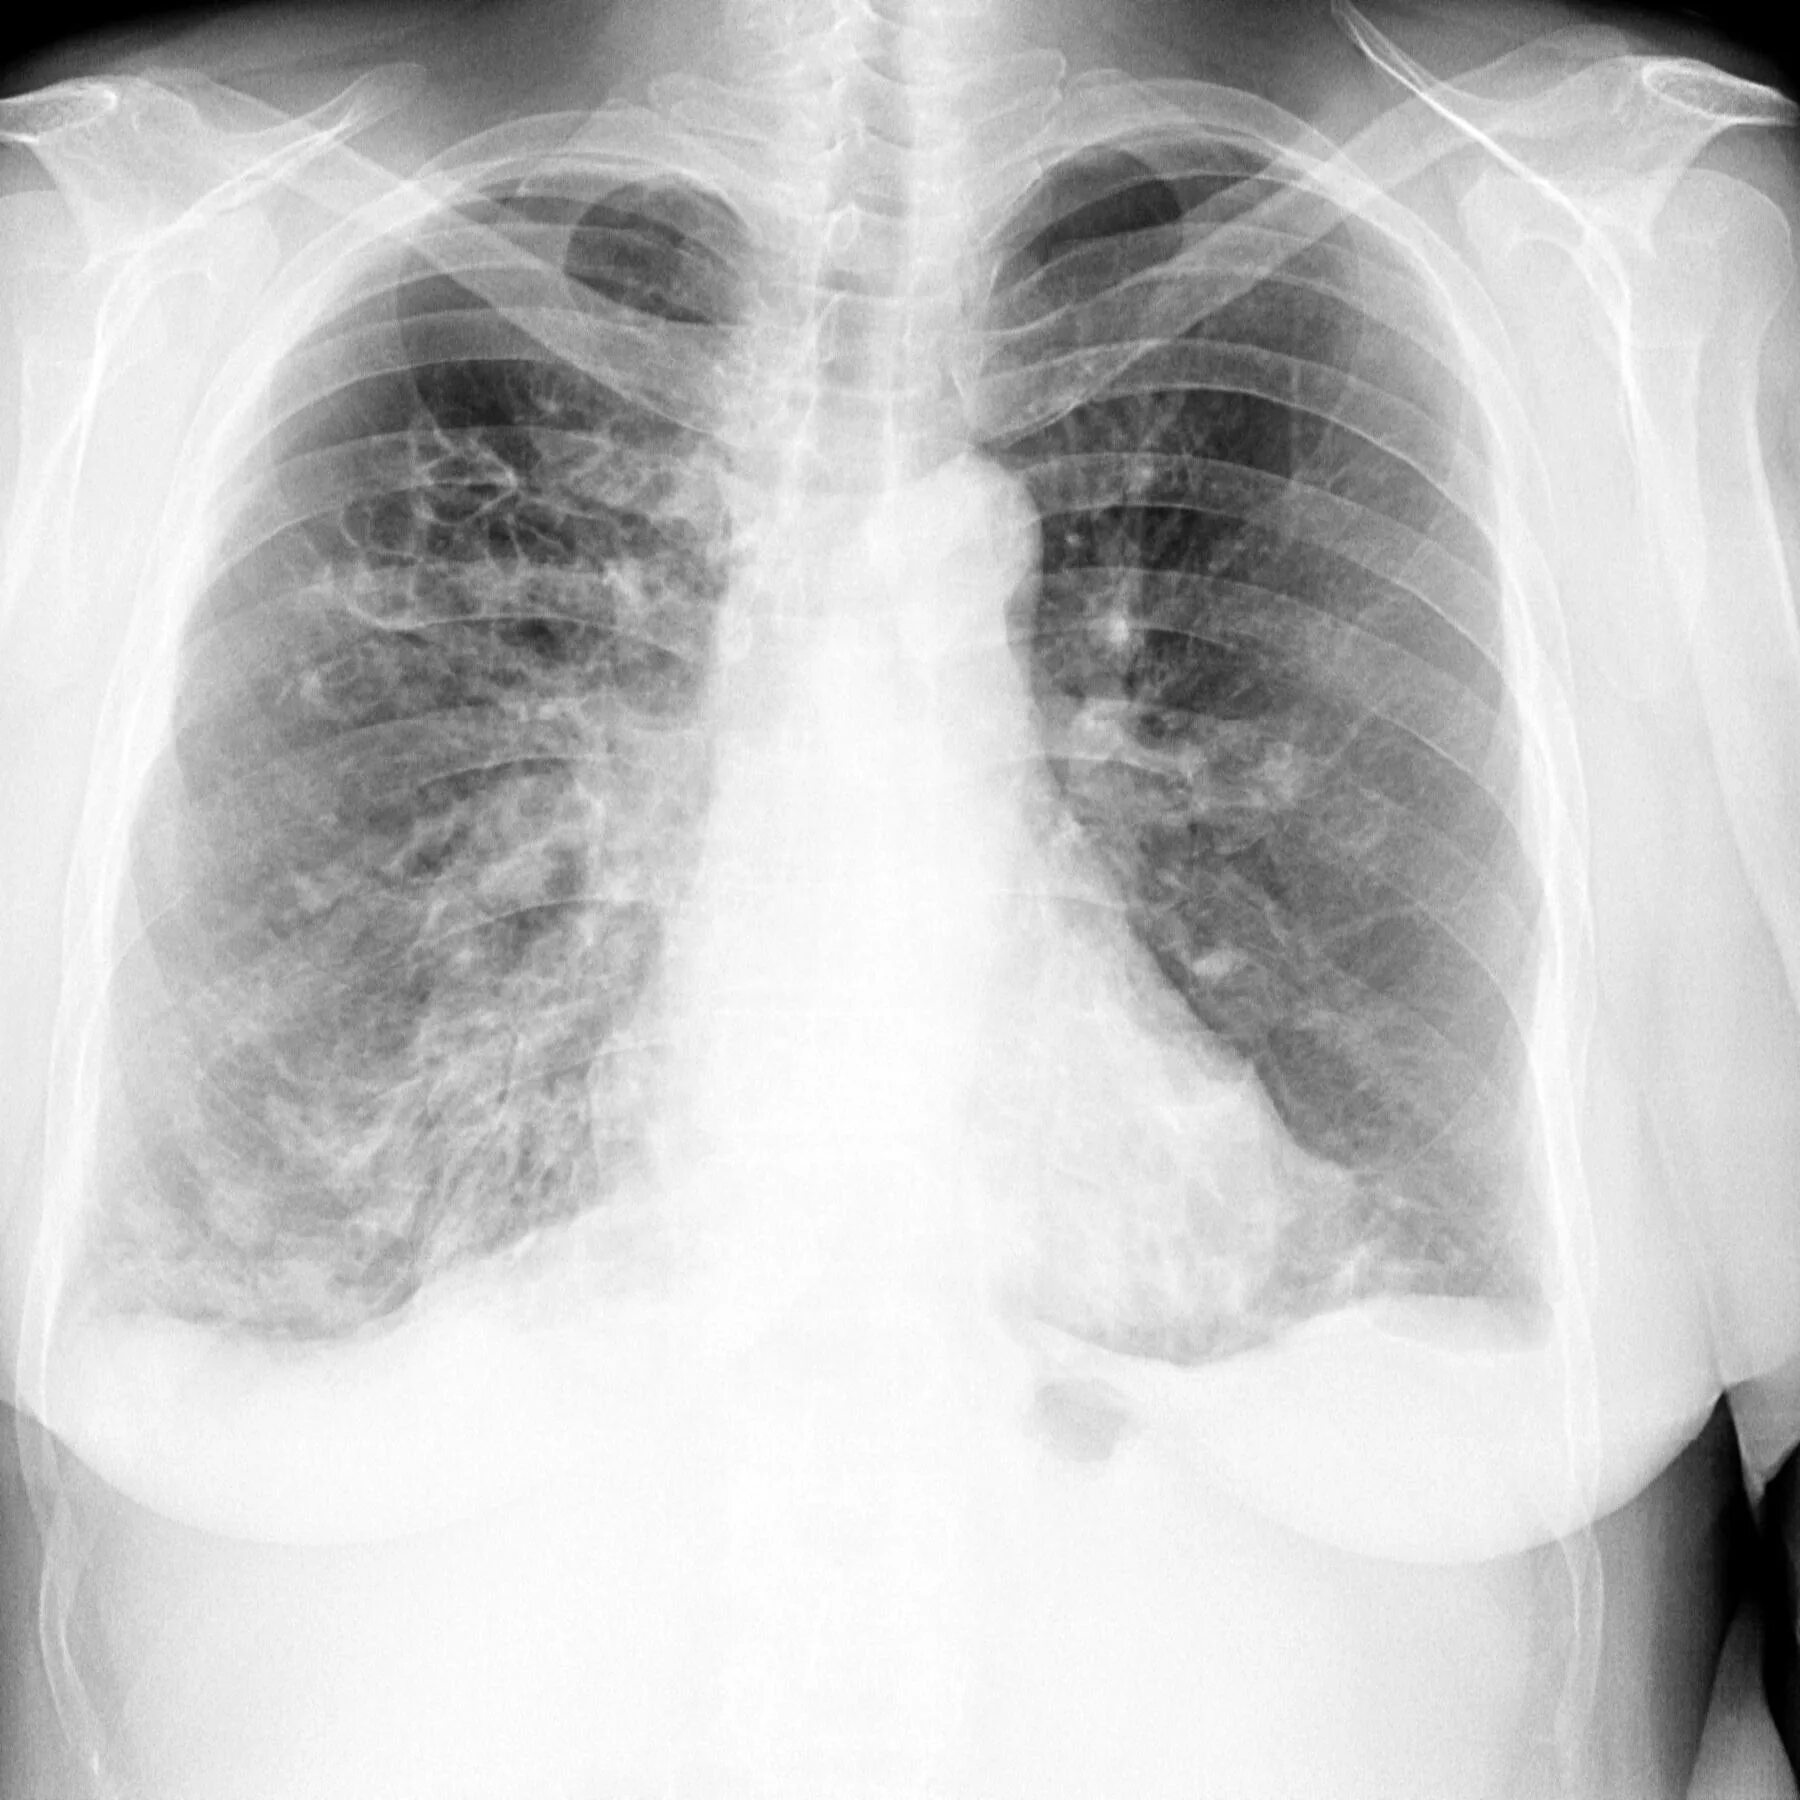

Бронхоэктазия